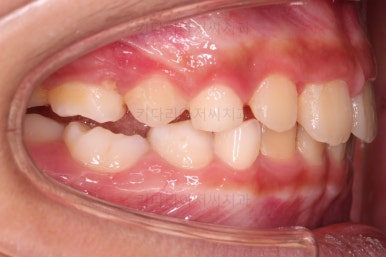

전후사진을 비교해 보겠습니다.

왼쪽이 부산어린이돌출입교정 치료 전, 오른쪽이 치료 후 입니다.

위치가 나빴던 앞니가 제위치로 갔고, 위아래 앞니도 서로 가까워졌어요.

앵글씨 2급 부정교합이 개선된거죠.

아래턱-위턱이 차이날 때 필연적으로 생기는 과개교합(앞니가 서로 깊게 맞물리는 교합)도 개선되었고요.

입이 튀어나와 보이던 모습도 완벽히 개선되었어요.

아래턱이 작아보이던 모습독 개선되었고 입도 편안하게 다물어져요.

턱의 위치가 잘못되어 결과적으로 보이던 "입이 튀어나온 모습, 윗니가 튀어나온 모습"이 턱뼈의 위치를 바로 잡아줌으로써 개선이 된거죠.